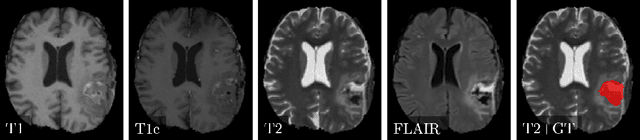

Abstract:Deep learning for regression tasks on medical imaging data has shown promising results. However, compared to other approaches, their power is strongly linked to the dataset size. In this study, we evaluate 3D-convolutional neural networks (CNNs) and classical regression methods with hand-crafted features for survival time regression of patients with high grade brain tumors. The tested CNNs for regression showed promising but unstable results. The best performing deep learning approach reached an accuracy of 51.5% on held-out samples of the training set. All tested deep learning experiments were outperformed by a Support Vector Classifier (SVC) using 30 radiomic features. The investigated features included intensity, shape, location and deep features. The submitted method to the BraTS 2018 survival prediction challenge is an ensemble of SVCs, which reached a cross-validated accuracy of 72.2% on the BraTS 2018 training set, 57.1% on the validation set, and 42.9% on the testing set. The results suggest that more training data is necessary for a stable performance of a CNN model for direct regression from magnetic resonance images, and that non-imaging clinical patient information is crucial along with imaging information.